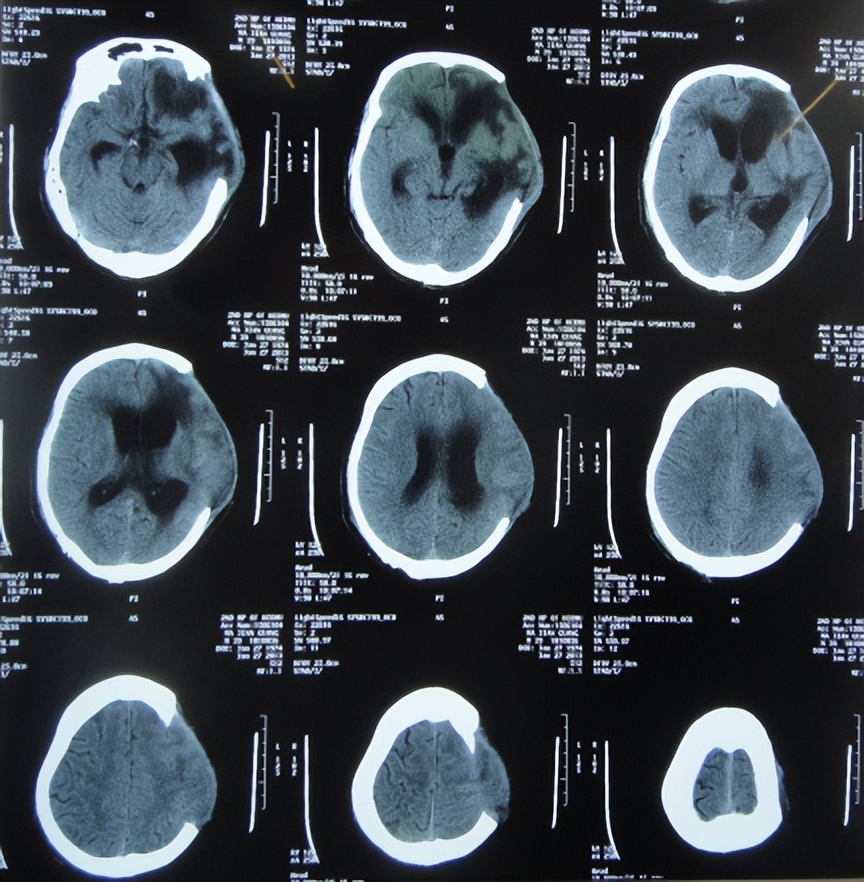

2013年3月5日(开颅术后88天,反复脑积水脑膨出35天)转住入李小勇脑脊液科;入院时:卧床昏迷;刺痛可睁眼、无发音;刺痛左侧肢体可屈曲、右侧肢体肌张力增高;局部颅骨缺损;左额颞顶区骨窗组织膨出、张力较高,左额颞顶区手术切口多处破溃、伴有脓性渗出物;双侧瞳孔对光反射弱,留置鼻饲管;大小便*禁失**( 图-11 )。

入院时查头颅CT示脑积水,左额颞顶及右枕开颅术后、伴局部颅骨缺损,左额颞顶区骨窗脑组织膨出明显、伴片状低密度灶( 图-12 )。

图-12: 2013年3月5日头颅CT

入院当天进行了脑室外引流术。术后次日查头颅CT示脑室缩小,脑膨隆变基本正常( 图-13 )。

图-13: 2013年3月6日头颅CT

脑脊液各项指标化验正常后于2013年3月26日(治疗21天),进行了左侧脑室-腹腔分流术( 图-14 )。

图-14: 2013年3月26日头颅CT